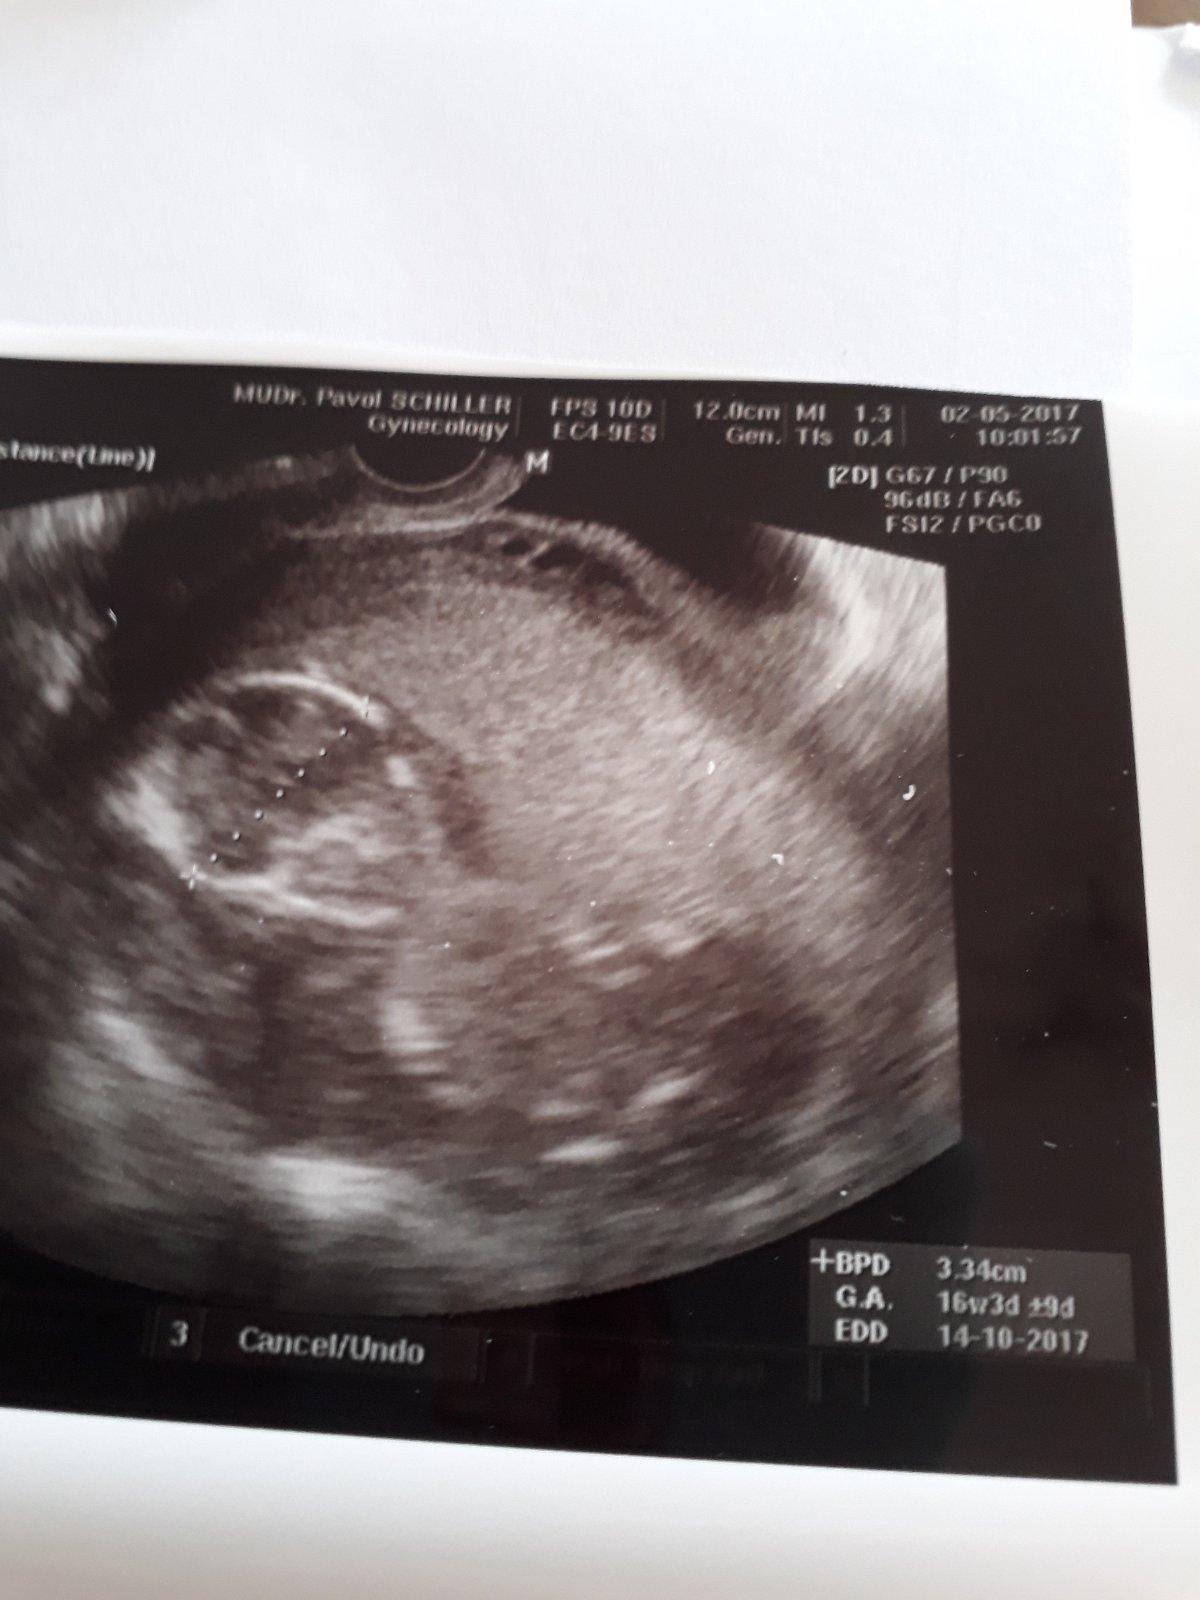

Bola som.dnes rano u svojho doktora tak vsetko je v poriadku,hematom zmizol len treba sledovat aby sa inde neobjavil. Kludovy rezim nadalej. TP mam na 11.12 ale ja viem ze to bude neskor 🙂 prva poradňa 30.5 snad bude aj foto,lebo zatial mam iba tehotensku knizku

@gabcca Tak super, že sa ti ten hematóm tak rýchlo vstrebal 😊 11.12.? :O To nejaký moc skorý termín ti vypočítal 😊 Ako vyzeralo bábo na ultrazvuku? 😊

@nikuskaniki jej krasny pohlad ked ukazal mimco ako tam si lezka a srdiecko bije 🙂 no vypocital podla ms a inak som dnes 6+3